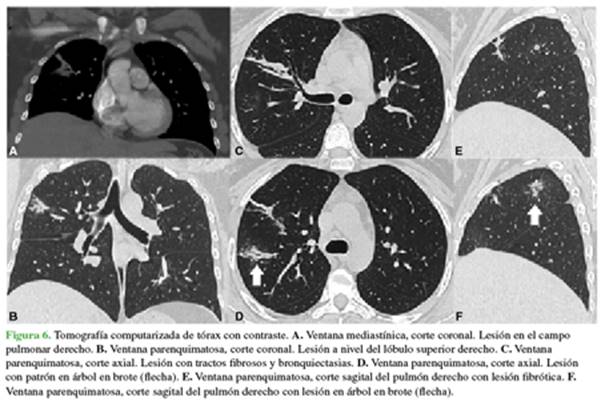

Con los resultados de la evaluación respiratoria, se decidió completar los estudios con una tomografía computarizada de tórax con contraste que mostró una condensación con trayectos lineales densos y broncograma aéreo, nodulillos subpleurales con un patrón en árbol en brote (Figura 6).